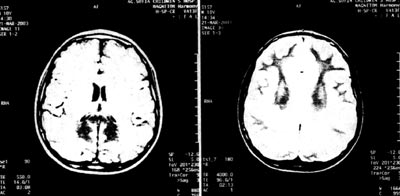

Εικόνα 1.

ΜRΙ εγκεφάλου.

Παθολογικό σήμα σε οπίσθια περικοιλιακή λευκή ουσία.

Επίσης, διενεργήθηκε εκ νέου μαγνητική τομογραφία εγκεφάλου, η οποία έδειξε χαρακτηριστικά συμμετρικές αλλοιώσεις με παθολογική ένταση, που αφορούν στην οπίσθια περικοιλιακή λευκή ουσία και το σπληνίο του μεσολοβίου, όπως φαίνεται στην εικόνα 1.